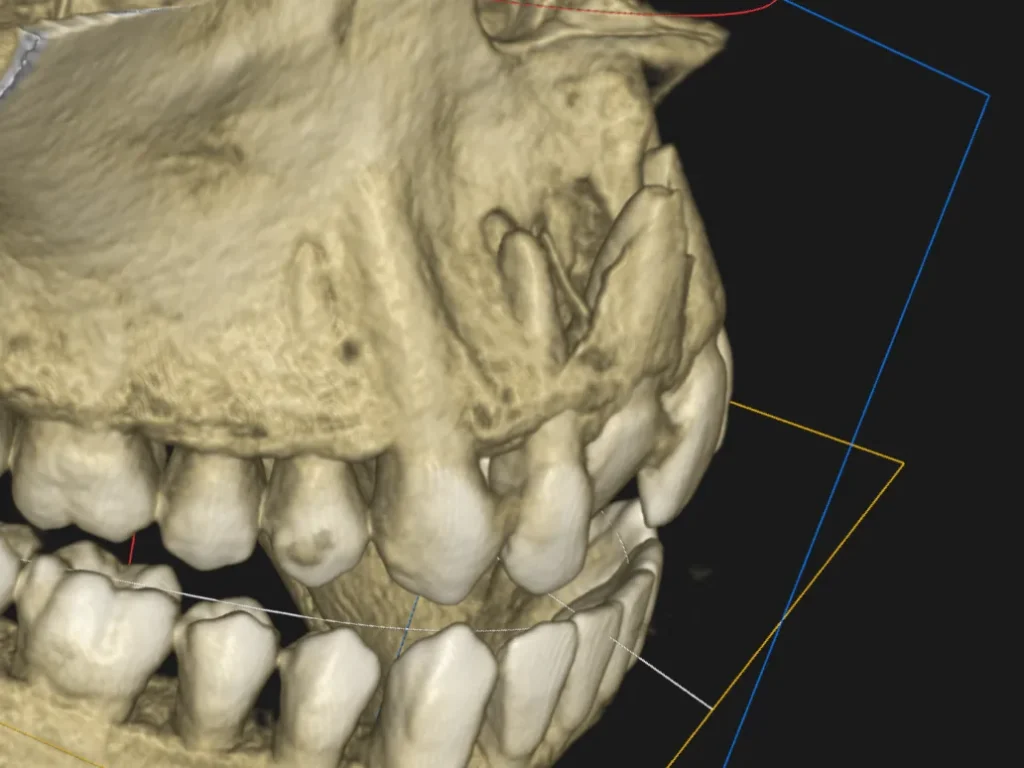

Diagnostyka radiologiczna pozwala ocenić stopień uszkodzenia:

- Zdjęcia punktowe (RVG) – standardowe badanie pokazujące stan korzenia i okolicznych tkanek

- Zdjęcie zgryzowe – szczególnie przydatne u małych dzieci, łatwiejsze do wykonania

- Zdjęcie panoramiczne – przegląd całego uzębienia i struktur kostnych 2D

- Tomografia stożkowa CBCT – zaawansowany przegląd uzębienia i struktur kostnych 3D

- Ocenia się: ustawienie korzenia, poszerzenie lub zwężenie szpary ozębnej, ewentualne złamanie zęba lub kości wyrostka zębodołowego

- U dzieci kluczowa jest ocena położenia zawiązka zęba stałego względem korzenia uszkodzonego mleczaka

Tomografia CBCT stosowana jest w niektórych przypadkach – przy podejrzeniu złamania kości szczęki, niejednoznacznym obrazie 2D lub planowaniu leczenia chirurgicznego. Zawsze z uwzględnieniem zasady ALARA (minimalna konieczna dawka promieniowania).